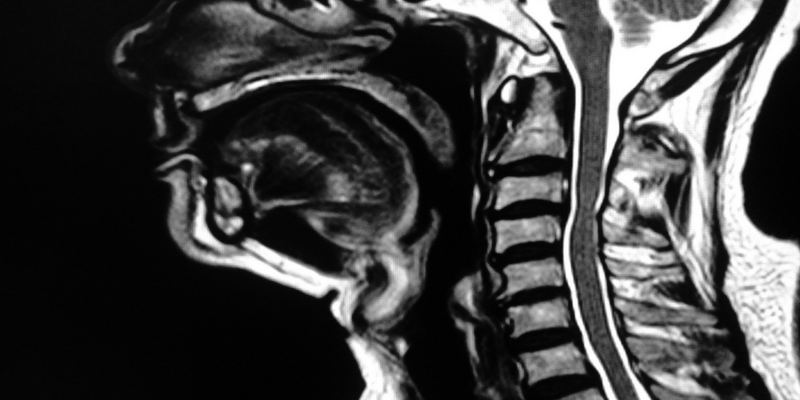

What is a Cervical Herniated Disc?

A slipped disc in your neck is medically referred to as a Cervical Herniated Disc.

An intervertebral disc is a spongy shock absorbing tissue located between each bone in the spine.

When a disc bulges or protrudes, the outer casing of the disc ( the annular) stretches, allowing the disc to change shape and herniate.

This shape change can put pressure on surrounding tissues such as nerve, causing pain and inflammation.